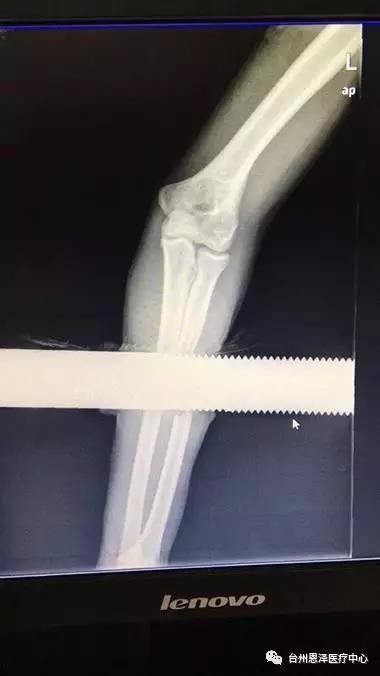

经测量贯穿松平手臂的实心钢棒长1.3米,直径6厘米。

接着沿伤口两侧作纵形切开,充分显露出铁棍周围的肌肉和神经,洪海南医生负责牵开,以免去除棍子时将肌肉与神经卷入,再谨慎地将棍子及衣服碎片从肌肉里取出来。这样,左前臂中段形成了一个空洞。仔细探查空洞周围组织,发现左桡骨中段已缺损伴周围肌肉的严重损伤,但尺骨是完整的,前臂两大神经(正中神经和尺神经)只是挫伤,连续性存在。

钢棒被一寸一寸地分离出来……经过两个小时的紧张手术,钢棒终于成功取出。医生马上对伤口进行清创处理,切除挫伤污染的皮肤及肌肉组织,咬除桡骨断端污染的骨组织,然后清洗伤口,最后进行伤口缝合,用石膏外固定。